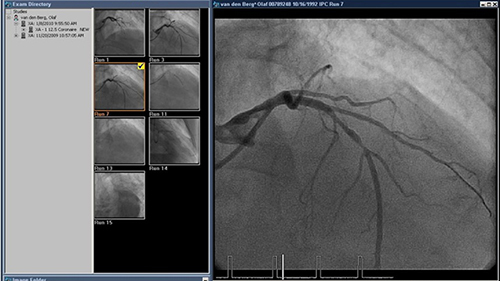

Xcelera is a robust multimodality cardiology image management, analysis and reporting solution that provides patient centric access to cardiology data and examinations.

Integrates all relevant images and information together in an interactive, intuitive and procedurally relevant way to expand clinical capabilities and enhance real time cross functional communication.